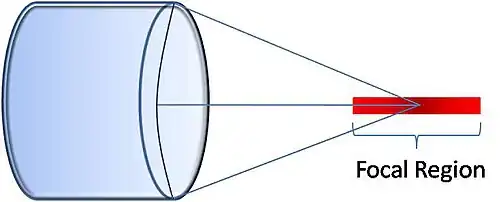

Focused Transducer

A spherically focused transducer is most sensitive to thermoacoustic waves originating along a line passing through its focal point. Time-of-flight information is used to estimate the thermoacoustic signal strength along this line. A 2D image can be assembled a line-at-a-time by translating the focused transducer laterally along a linear path. A 3D image can be built up by scanning the transducer along a rectilinear path within a 2D plane.[19][1] The ability to distinguish thermoacoustic signals along the line of focus (axial resolution) is superior to distinguishing thermoacoustic signals transverse to the line of focus (lateral resolution). For this reason the lateral spatial resolution is three- to four-times worse than the axial spatial resolution using this approach.